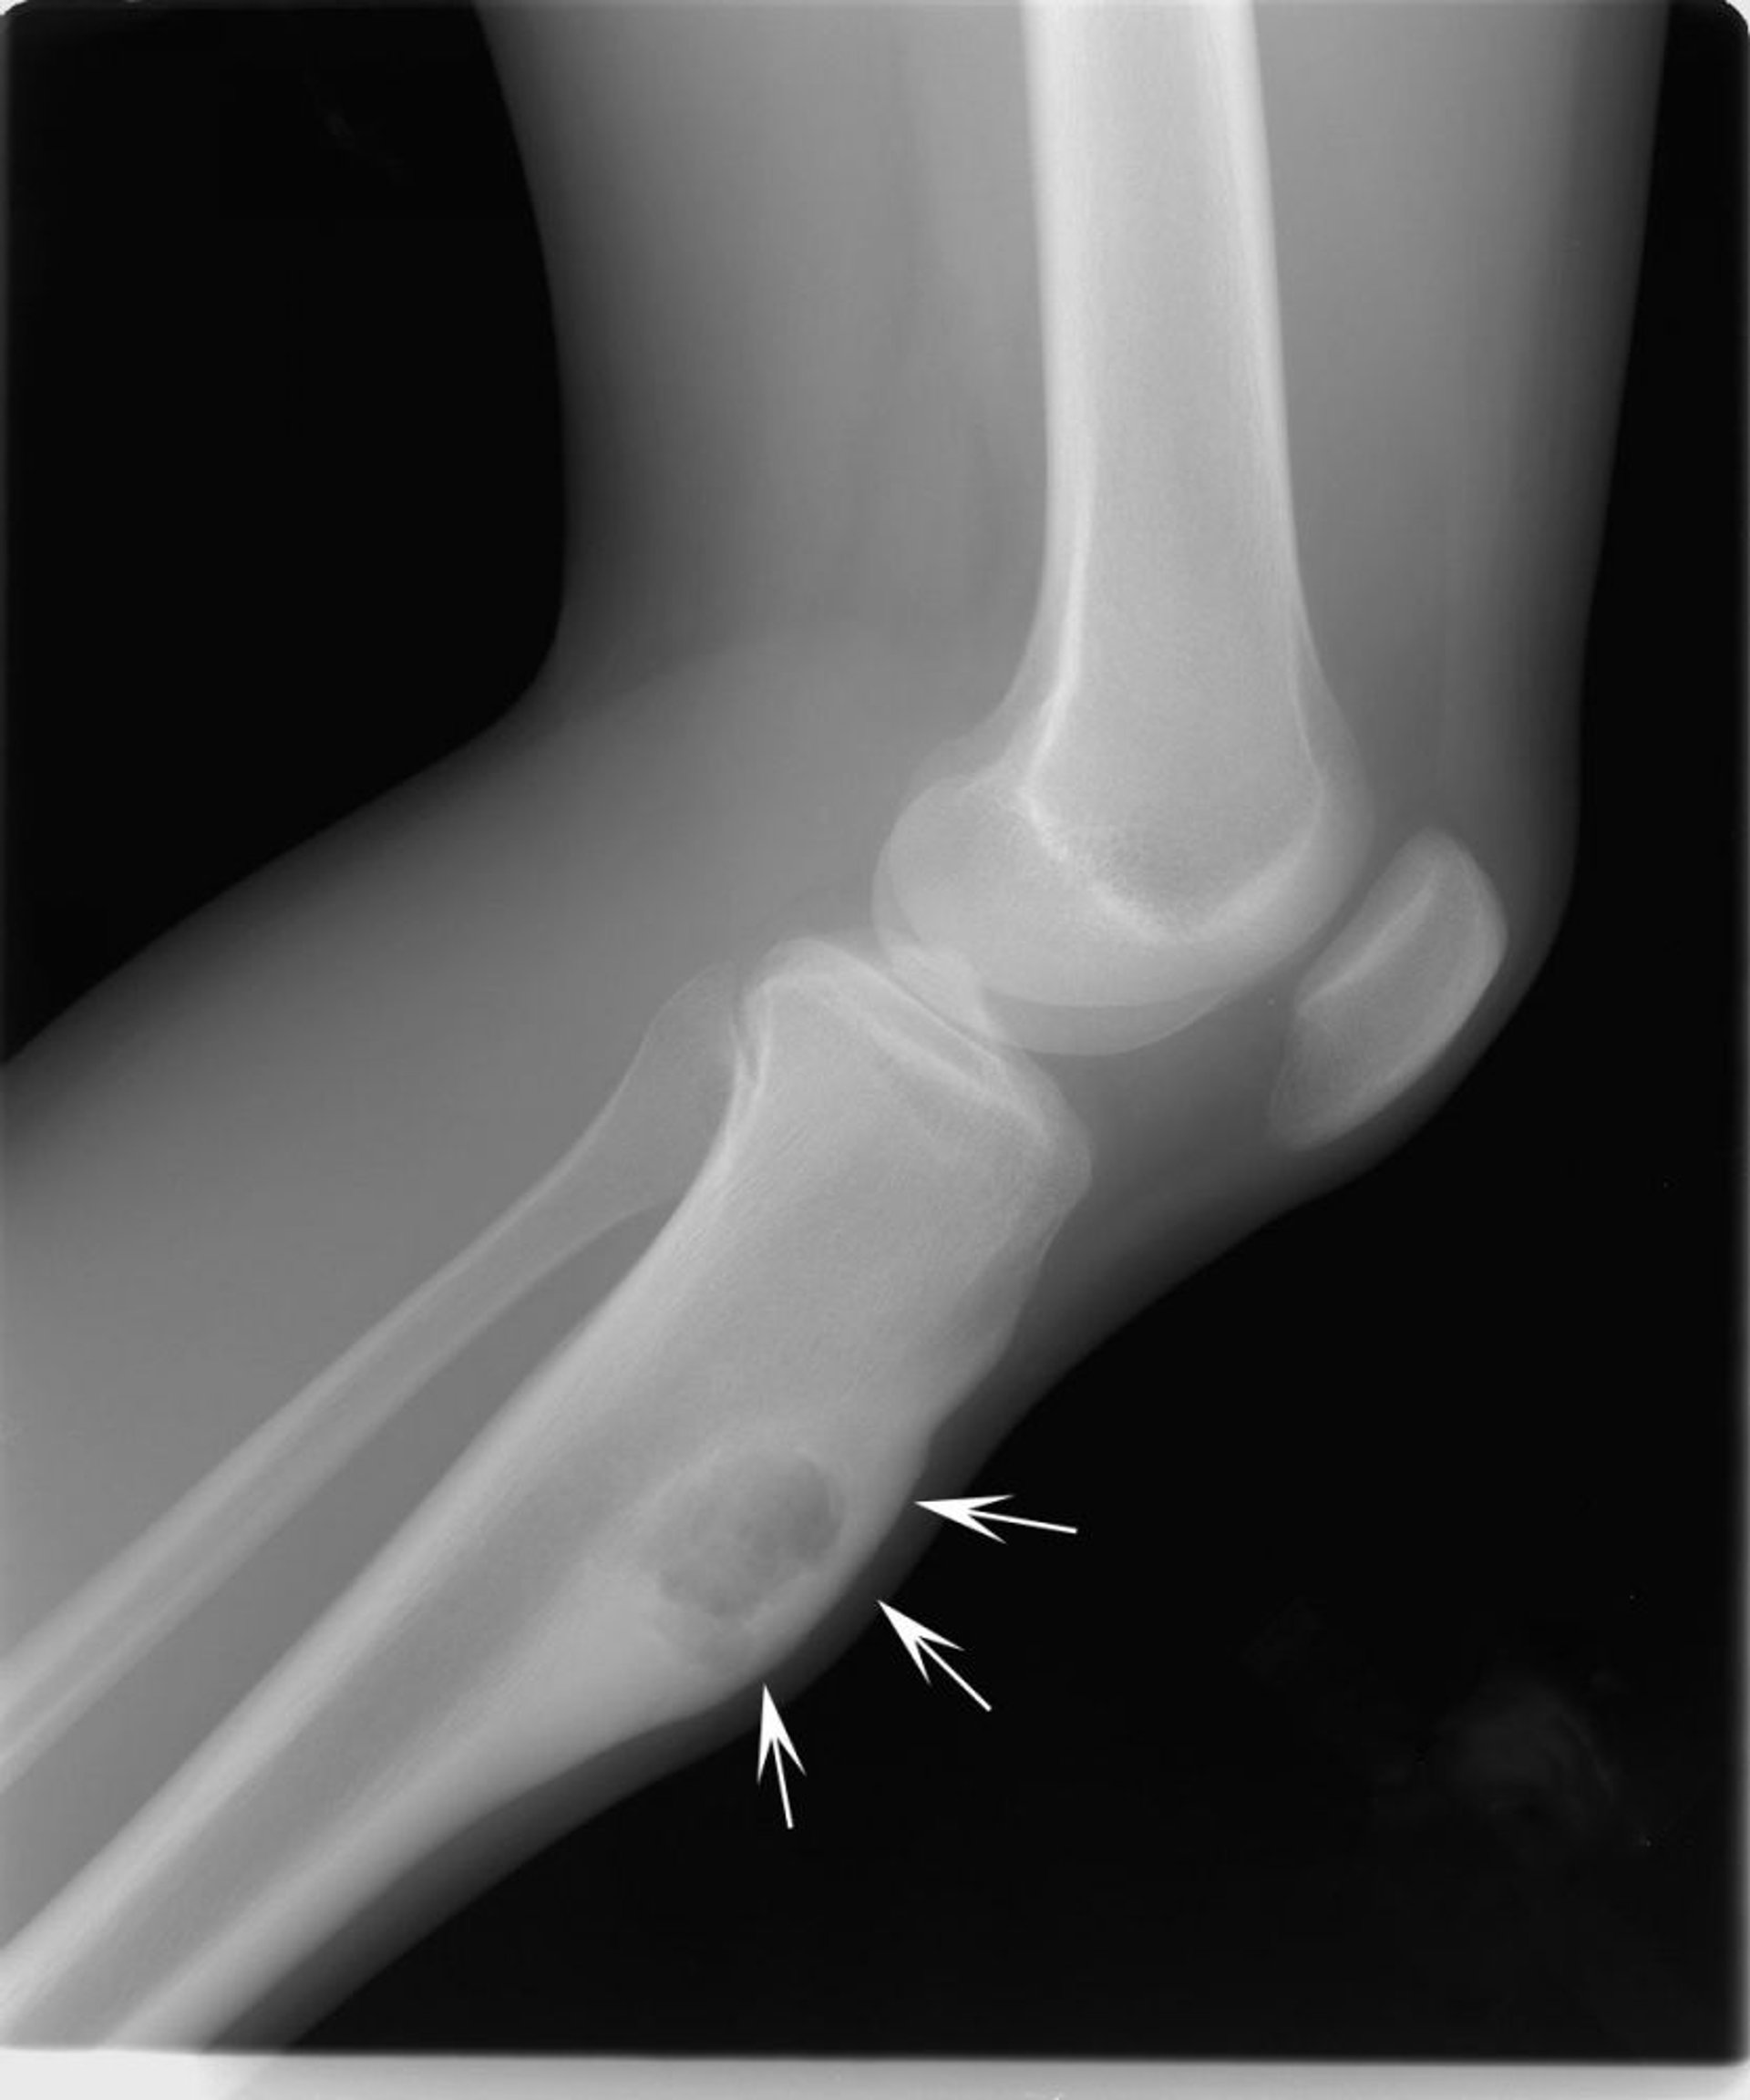

يوصي الأطبَّاءُ بإجراء صورةٍ بالأشعَّة السينيَّة لتشخيص الأورام الأروميَّة الغُضروفية، وقد يوصون بإجراء اختبارات تصوير أخرى، مثل التصوير بالرنين المغناطيسي.كما يقومون بأخذ عَيِّنَة نسيجيَّة للفحص تحت المجهر (خزعة).

تُظهر هذه الصورة الشعاعية للكتف وجود ورم أرومي غضروفي chondroblastoma في عظم الذراع في نهاية العظم (اتجاه الأسهم).

جرى استخدام الصورة بعد موافقة أصحابها Michael J.Joyce, MD, and Hakan Ilaslan, MD.